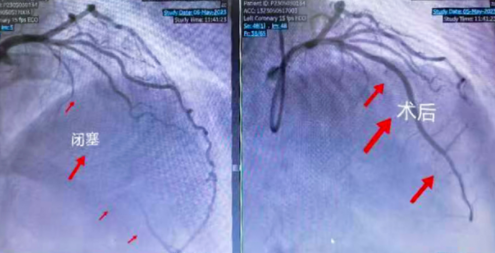

患者在我院介入导管室接受了冠状动脉造影检查。结果显示,患者LAD(前降支)近段闭塞100%,建议行经皮冠状动脉介入术(PCI)治疗。术中,吴强主任使用微导管辅助下XT导丝成功通过闭塞远端,但反复尝试预扩球囊,球囊通过LAD闭塞段困难,考虑病变处冠脉钙化严重,多次尝试预扩球囊未果后,被动选择冠脉内旋磨术,该病变钙化重,长病变,常规介入手段治疗困难,吴强主任冠脉介入团队迎难而上,经1.5旋磨头以13-15万转/min旋磨治疗后于LAD闭塞段成功植入3枚支架,手术顺利,术后解决了困扰患者多年的胸闷痛症状。